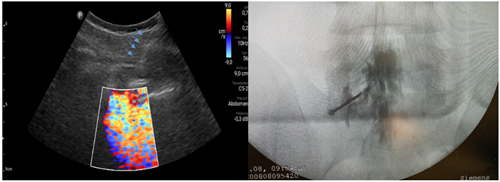

Pacientes y métodos: Un total de 25 pacientes con dolor radicular lumbosacro fueron seleccionados para recibir inyecciones epidurales interlaminares de esteroides en posición decúbito dorsal, utilizando la técnica ecoguiada en plano, en tiempo real, en eje corto o transversal. En todos los casos, un epidurograma de control fue realizado previo a la inyección de la solución de esteroides. El rendimiento de la técnica fue estudiado mediante la tasa de éxito de la misma, entendido como éxito a la obtención de un epidurograma sin necesidad de abandonar la técnica ecográfica en un tiempo menor a 10 minutos. El rendimiento del procedimiento fue estadísticamente evaluado por el método de la suma acumulativa (CUSUM), y la curva de aprendizaje aplicando este método fue construida.

Resultados: La distancia promedio desde la piel al complejo posterior evaluada por el escaneo ecográfico previo al procedimiento fue de 6,7 ± 1,8 cm. De los 25 procedimientos realizados, en 21 se alcanzó el espacio epidural sin ayuda de la fluoroscopia, en un tiempo promedio de 4,8 ± 1,2 minutos. Esto constituye una tasa de éxito del 84 %. En los cuatro procedimientos restantes el espacio epidural fue alcanzado con éxito mediante el uso complementario de la fluoroscopia.

Figura 2